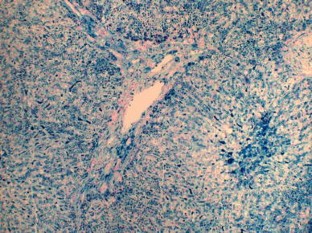

Reticuloendothelial iron overload is associated with secondary hemochromatosis including repeated transfusions and iron over-supplementation. Ferroportin disease B is a severe subtype of hereditary iron overload syndrome with an activated reticuloendothelial system. The iron exporter ferroportin may be insensitive to hepcidin 25 in this subtype. However, the interactions between the hepcidin–ferroportin system and modifiers of reticuloendothelial iron overload have not yet been elucidated. We describe two patients with iron overload conditions that were compatible with ferroportin disease B, but their genetic backgrounds and habitual states differed. Both patients had diabetes, periportal fibrosis with severe iron deposits in their hepatocytes and Kupffer cells, and adequate levels of circulating hepcidin 25. However, the first patient was heterozygous for a mutation in the FP gene and free from the acquired factors of iron overload, while the second patient was a heavy drinker with a heterozygous mutation in the TFR2 gene and no mutations in the FP gene. The first patient was the second reported case of ferroportin disease B in Japan. Our study on these 2 patients suggests that liver fibrosis associated with compound iron overload of reticuloendothelial cells and hepatocytes may occur via multi-etiological backgrounds.

Fig. 2